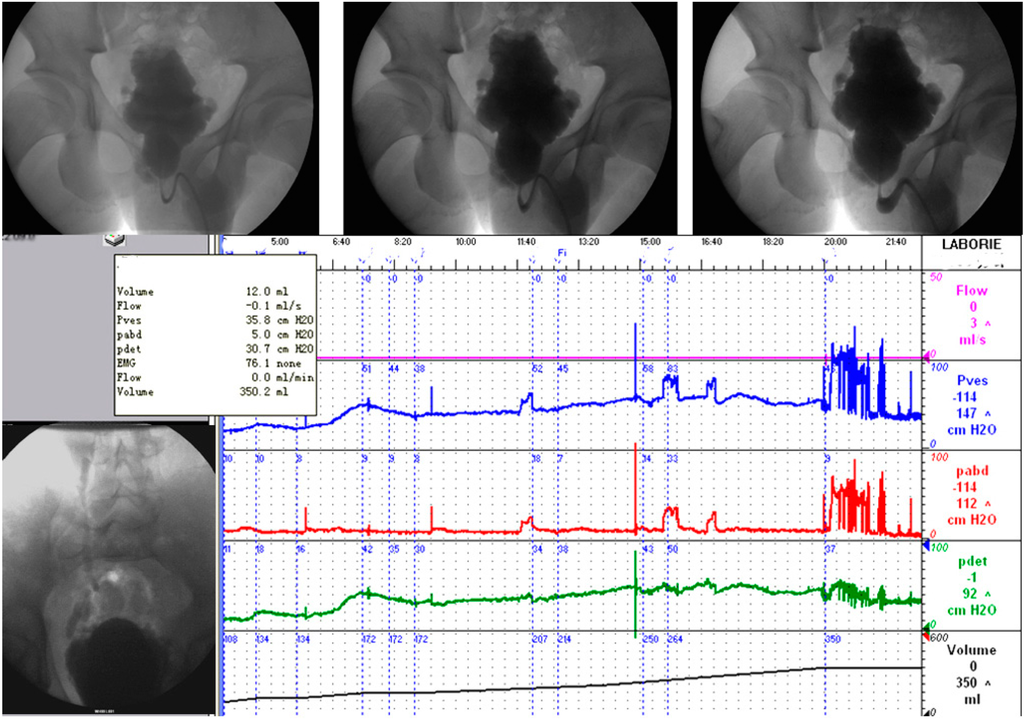

2.3. Urodynamics

- Schaefer, W.; Abrams, P.; Liao, L.M.; Mattiasson, A.; Pesce, F.; Spangberg, A.; Sterling, A.M.; Zinner, N.R.; van Kerrebroeck, P. Good urodynamic practices: Uroflowmetry, filling cystometry, and pressure-flow studies. Neurourol. Urodyn. 2002, 21, 261–274. [Google Scholar] [CrossRef] [PubMed]

- Liao, L.M.; Schaefer, W. Quantitative quality control during urodynamic studies with TVRs for cystometry in men with lower urinary tract symptoms suggestive of benign prostatic hyperplasia. Int. Urol. Nephrol. 2014, 46, 1301–1308. [Google Scholar] [CrossRef] [PubMed]

- Liao, L.M.; Schaefer, W. Qualitative quality control during urodynamic studies with TSPs for cystometry in men with lower urinary tract symptoms suggestive of benign prostatic hyperplasia. Int. Urol. Nephrol. 2014, 46, 1073–1079. [Google Scholar] [CrossRef] [PubMed]

- Liao, L.M.; Schaefer, W. Effects of retrospective quality control on pressure-flow data with computer-based urodynamic systems from men with benign prostatic hyperplasia. Asian J. Androl. 2007, 9, 771–780. [Google Scholar] [CrossRef] [PubMed]